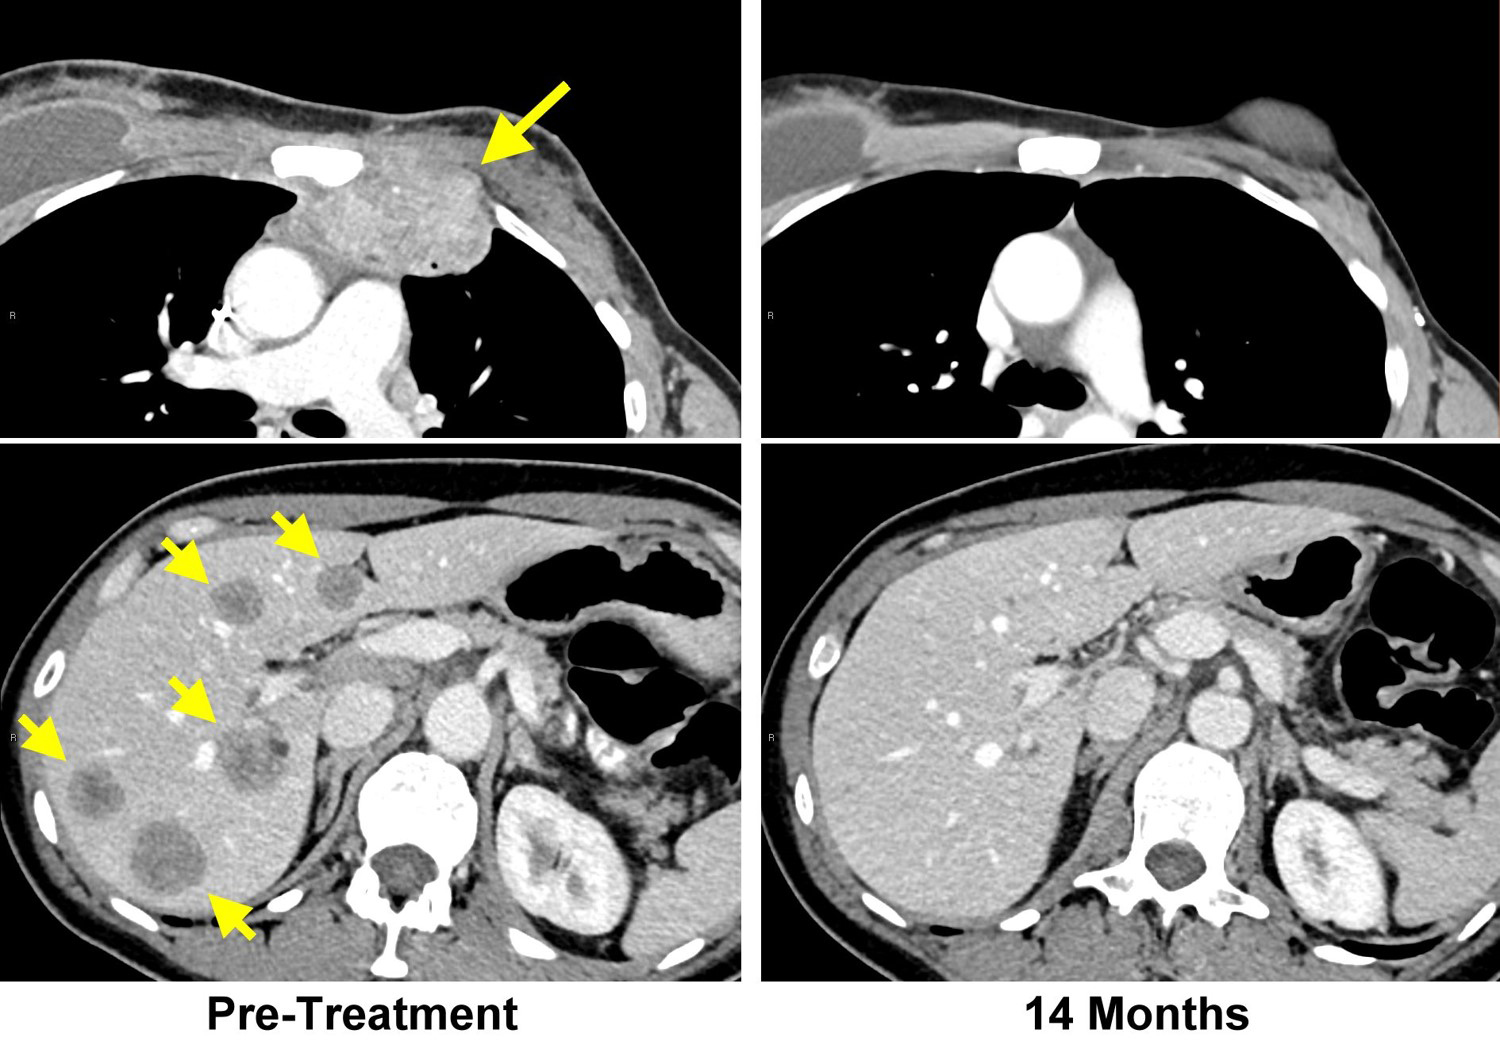

A patient with metastatic breast cancer came to the trial after receiving multiple treatments, including several chemotherapy and hormonal treatments, that had not stopped her cancer from progressing. To treat her, the researchers sequenced DNA and RNA from one of her tumors, as well as normal tissue to see which mutations were unique to her cancer, and identified 62 different mutations in her tumor cells.

The researchers then tested different TILs from the patient to find those that recognized one or more of these mutated proteins. TILs recognized four of the mutant proteins, and the TILs then were expanded and infused back into the patient. She was also given the checkpoint inhibitor pembrolizumab to prevent the possible inactivation of the infused T cells by factors in the tumor microenvironment. After the treatment, all of this patient’s cancer disappeared and has not returned more than 22 months later.